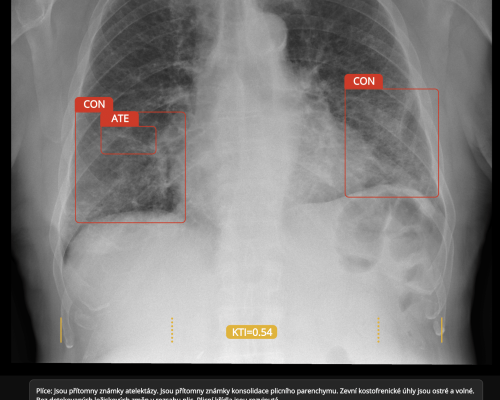

Český program časného záchytu karcinomu plic, spuštěný v roce 2022, uzavírá pilotní fázi a vstupuje do závěrečného hodnocení. Do konce roku 2024 bylo…